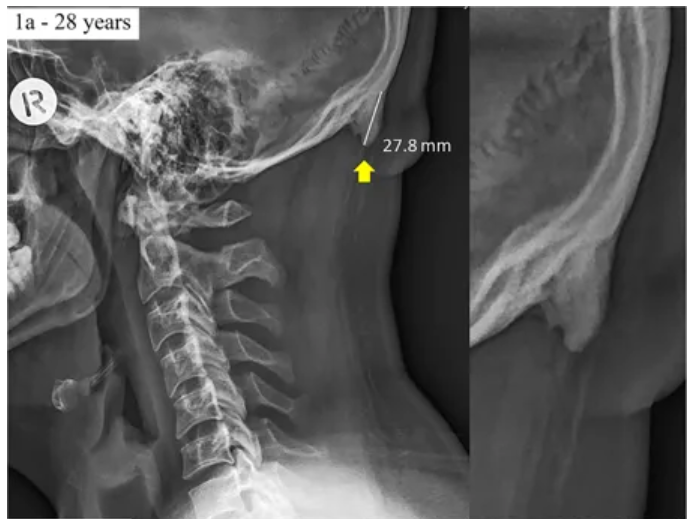

Теория впервые возникла еще в 2016 году, когда Шахар и Сэйерс в ходе рентгеновского исследования заметили у целого ряда пациентов в возрасте от 18 до 30 лет выпирающий костный нарост в той области, где к черепу крепятся мышцы шеи. Величина наростов в среднем составляла от 10 до 30 миллиметров – пациенты могли сами нащупать выпуклость рукой. Всего было задокументировано 218 подобных случаев.

«Эти результаты примечательны потому, что, как правило, наросты образуются в течение многих лет; их чаще можно наблюдать у пожилых людей, — поясняет доктор Шахар. – Важно понимать, что в большинстве случаев костные шпоры достигают размера всего в несколько миллиметров, здесь же мы видим отростки до трех сантиметров у молодежи».